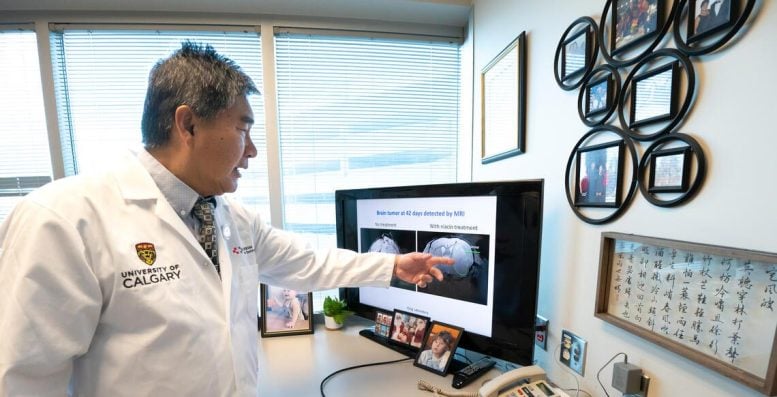

L’aggregazione di cellule tumorali nel glioblastoma senza trattamento, a sinistra, e come la niacina impedisce l’aggregazione cellulare. Credito: Per gentile concessione del laboratorio Yong.

Ripristinare l’attacco immunitario contro i tumori

“Normalmente, il sistema immunitario cerca di contrastare e prevenire la crescita del tumore; tuttavia, questo tumore cerebrale sopprime il sistema immunitario”, afferma Yong, Professore alla Cumming School of Medicine (CSM). “Il trattamento con niacina ringiovanisce le cellule immunitarie in modo che possano svolgere la loro funzione, ovvero attaccare e uccidere le cellule tumorali. La considero una continua ‘battaglia per il cervello’ “.